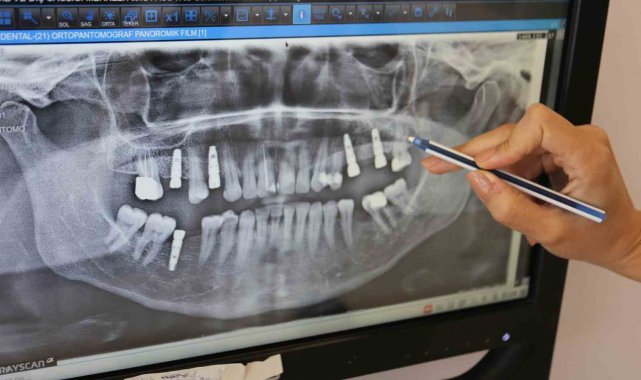

Günde yaklaşık bin kişiye poliklinik hizmeti veren Manisa Ağız ve Diş Sağlığı Merkezi'nde 'İmplant' uygulaması başarılı bir şekilde devam ediyor. Merkezde son 7 ayda 164 implant uygulamasının yapıldığı öğrenildi.

Şu zamana kadar da başarıyla 164 adet implantı ağıza uyguladıklarını ifade eden Başhekim Dt. Kaya, üst yapıları da zirkonyum olarak hastalara teslim edilerek, hastalar tarafından kullanıldığını kaydetti.

Başhekim Dt. Kaya, "Tabii bunların dışında bu ilk 6 ayda 170 adet implantı da başarıyla uyguladık ve hala ağızda olan implantlarımız var. Kemiğe kaynadığı zaman da bunların üst yapılarını da zirkonyum olarak takacağız." diye konuştu.